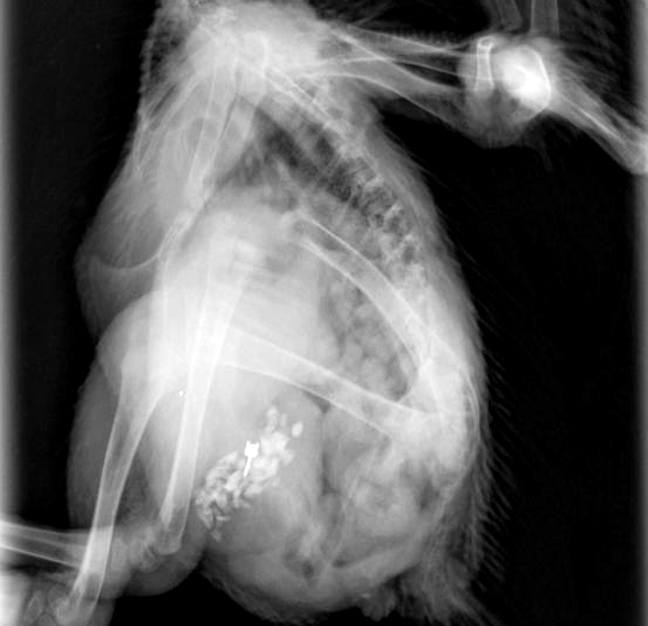

«Αλλά ένας φίλος κτηνίατρος μας είπε πως μπορεί να έχει κολλήσει στο στομάχι της Sarah, κάτι που επιβεβαιώθηκε από την ακτινογραφία», εξήγησε η Claire.

Οι κτηνίατροι εξήγησαν στην Claire πως το σκουλαρίκι έχει «σκαλώσει» στο στομάχι της 6 μηνών Sarah και δεν πρόκειται να βγει δια της… γνωστής οδού.